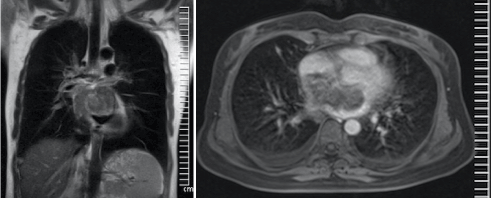

After 5 months of first admission, chest roentgenography showed the bilateral reticular opacities (Figure 2) and HRCT showed the multiple pulmonary nodules (Figure 3). We suspected from malignancy and F-18 FDG PET/CT scan performed to identify primary tumour and there was malignant uptake in left iliac bone uptake (Figure 4A and 4B). We perform the thoracic MR to evaluate the mediastinal structures and there is a large mass lesion in the right atrium (Figure 5).  Intracardiac mass lesion was confirmed at 3rd echocardiography (Figure 6). Cardiac sarcoma was defined with histopathologic examination of iliac bone biopsy.

Figure 5A and 5B. Contrast-enhanced Thoracic MR images showing the intracardiac mass.

Exertional dyspnoea was main symptom in our case. First radiologic finding was bilaterally pleural effusion. Thoracic CT scans and echocardiographic examinations were failed to identification of intracardiac lesion. F-18 FDG PET/CT scan missed lesion due to physiological cardiac uptake in the lesion. Contrast-enhanced Thoracic MR images showed the intracardiac mass and it was confirmed with re-performed echocardiography carefully. And, time of diagnosis of cardiac sarcoma was 5 months after the first admission of clinic.